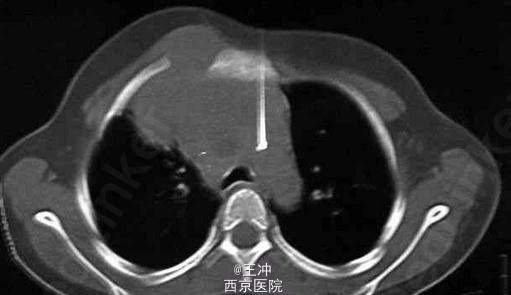

患者,女性,7岁,胸部右侧出现肿块有3个月。

病变部位轻度压痛,大小约为3 cm。CT扫描显示有一大的肿瘤,由皮下脂肪组织延伸至前纵隔,伴软组织受累。